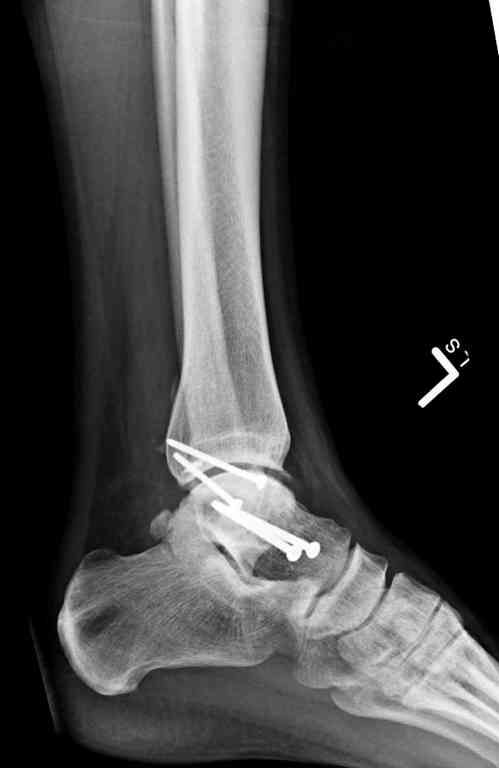

Второй случай прооперирован вчера.

10 дней назад поступил с открытым повреждением медиальной лодыжки и переломо вывихом таранной кости. Ургентно сделана репозиция с наложением наружного фиксатора + Irrigation&Debridment.

Во время репозиции выявили повреждение заднего сухожилия м. тибиалис и задней большеберцовой артерии. Медиальную рану удалось закрыть частично и установлен вакуум.

Дважды провели Irrigation&Debridment с заменой вакуума.

Вчера провели фиксацию.

Из-за многооскольчатости дистальной части малоберцовой, где невозможно было провести фиксацию шурупами, перелом зафиксирован подпирающей пластиной, которая должна служить дополнением отсутствующей дистальной части малоберцовой (lateral cortex substitute).

Для стабильности два шурупа на синдесмоз.

Медиальную рану с приближенными краями продолжаем вакуумировать (KCI). Наружный фиксатор оставлен на пару недель, надеюсь, небольшая рана будет гранулировать и закроется без кожной пластики. Фиксация медиальной ложыжки не планируется.